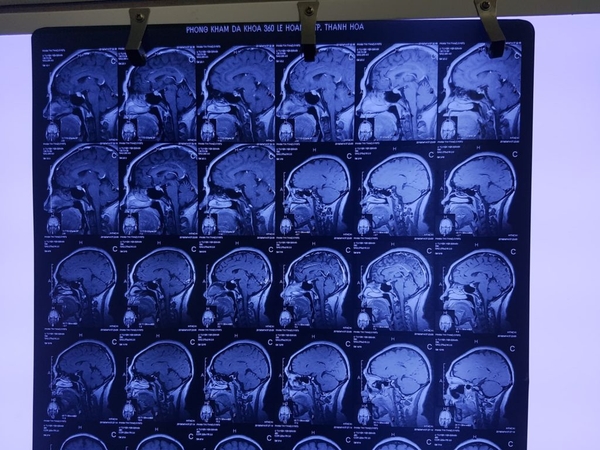

Tháng 4/2018 chụp MRI sọ não sau uống KILCEL 3 tháng thấy khối U tuyến yên teo nhỏ.

Kết quả sau uống KILCEL 500mg